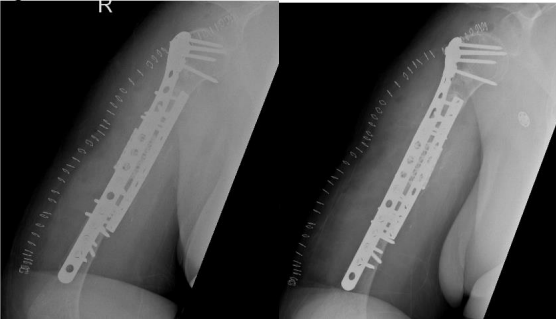

Options was discussed and The decision was made to take the patient for surgery for the third time “second revision” on17 June 2019. The sclerotic bone was excised, which accounted for 2.5 cm in length, and replaced with a tricortical iliac crest strut autograft, cancellous graft, and putty bone substitute. The same plate was applied, and new screws were used to hold the graft in place. The remaining screws were inserted, and the device was stable intraoperatively. Postoperative radiographs are shown in Figure 4.

Figure 4

One month postoperatively, on 29 July 2018 the patient heard a pop sound and felt sudden pain while performing physiotherapy. Examination revealed slight motion at the fracture site associated with pain. Radiographs showed four broken screws with displacement of the plate distally (Figure 5).

Figure 05